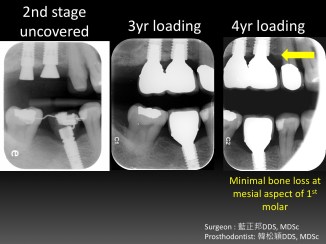

Vertical Ridge Augmentation – Case A